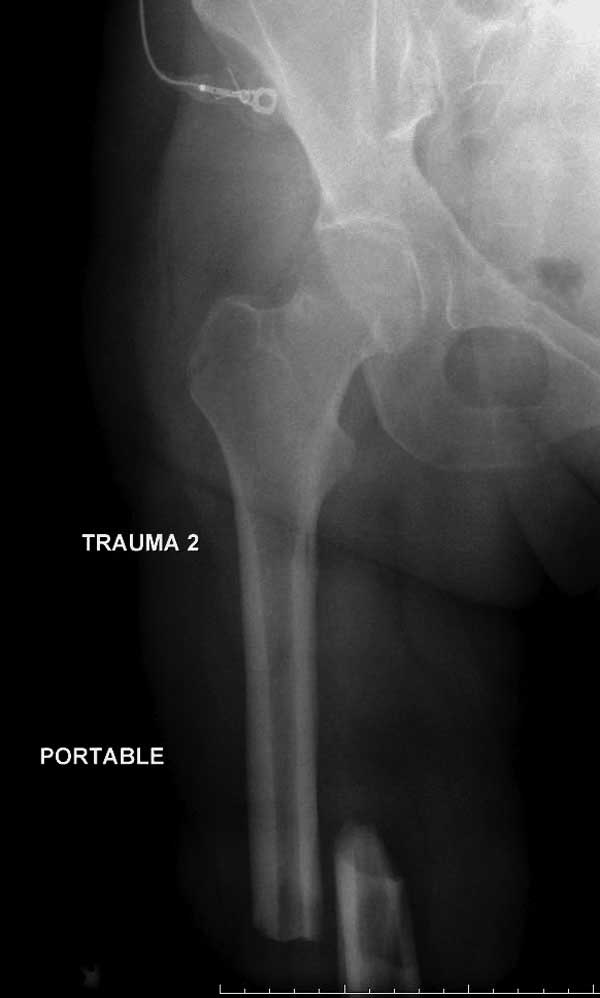

В диагноз еще необходимо внести закрытую (?) ротационно-нестабильную травму таза с переломами лонных седалищных костей, боковой массы крестца справа.

Напрашивается реализация тактики многоэтапного хирургического лечения ("damage control"): фиксация правого бедра, правого голеностопного сустава, таза стержневыми аппаратами внешней фиксации с выполнением "ориентировочной" ручной репозиции. Возможна и фиксация левого бедра с соединением бедренной и тазовой штанг и выполнение вытяжения (независимое скелетное вытяжение). Дальнейшие действия - по стабилизации показателей гемодинамики,газообмена,гемокоагуляции, воспалительного ответа.

Трудно выбрать приоритет, когда имеется одинаковые по значимости, по сложности повреждения и с вовлечением различной локализации. У пожилых переломо-вывих головки бедра можно было бы проигнорировать, но у молодых такое решение привело бы к катастрофе, и поэтому приоритет первичной фиксации отдали решению переломо-вывиха таранной кости и головки бедра.

Вообщем.., больная поступает около 2.00 дня и дальнейщая хронология: 2.27 PМ рентген грудной клетки; 2.54 РМ рентген бедра; 2.53-3.06 КТ скан, всего около 2000 срезов. Из-за беспокойства пациента (алкоголь), множественные переломы ребер – трубка в превральную полость и интубация. Около 3.45 в операционной эксплуараторная лапароскопия с последующим ушиванием брюшной полости.

Перелом позвоночника и боковую компрессию таза отнесли к стабильным переломам и не стали форсировать события до лучших времен...

Больная стабильная после хирургических мероприятии и получив добро, приступили к закрытому вправлению таранной кости с укладкой наружного фиксатора. Затем укладка больную на бок и открытый остеосинтез перелома-вывиха головки бедра.

По характеру повреждения головка находится сзади и напрашивается задний Кохер-Лангенбек доступ, но в заднем доступе имеется риск повреждения магистрального кровоснабжения головки a. circumflexa. Более щадящая trochanteric flip (digastric osteotomy) сохранит кровоснабжение и дасть возможность работу при вывихнутом суставе.

Остеосинтез бедра не стали делать из-за множественных переломов ребер с ушибом грудной клетки и поэтом у закончили фиксацию бедра наружным фиксатором.